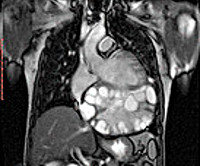

B67.9 Эхинококкоз других органов и неуточненный